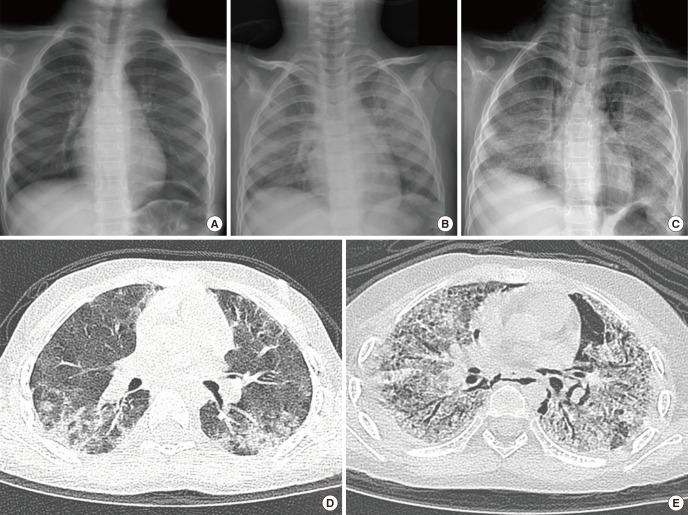

From 2006 to 2011, an outbreak of a particular type of childhood interstitial lung disease occurred in Korea. The condition was intractable and progressed to severe respiratory failure, with a high mortality rate. Moreover, in several familial cases, the disease affected young women and children simultaneously. Epidemiologic, animal, and post-interventional studies identified the cause as inhalation of humidifier disinfectants. Here, we report a 4-year-old girl who suffered from severe progressive respiratory failure. She could survive by 100 days of extracorporeal membrane oxygenation support and finally, underwent heart-lung transplantation. This is the first successful pediatric heart-lung transplantation carried out in Korea.

2006年至2011年期间,韩国爆发了一种特殊类型的儿童间质性肺病。这种疾病难以治疗,会发展为严重的呼吸衰竭,死亡率很高。此外,在一些家族病例中,该疾病同时影响年轻女性和儿童。流行病学、动物实验和干预后研究确定病因是吸入加湿器消毒剂。在此,我们报告一名患有严重进行性呼吸衰竭的4岁女孩。她通过100天的体外膜肺氧合支持得以存活,最终接受了心肺移植。这是韩国首例成功的小儿心肺移植手术。